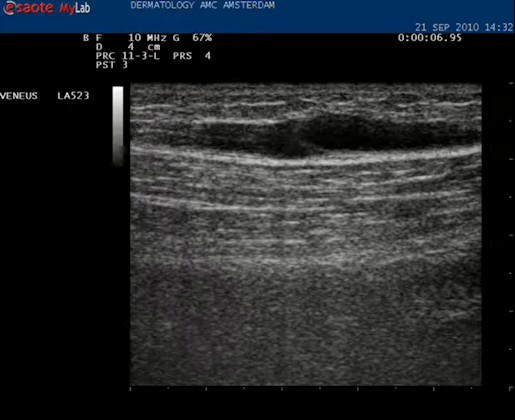

| Met de echokop dwars op de binnenkant van het bovenbeen wordt direct een hooggelegen (extrafasciaal gelegen) vena saphena magna gezien. De VSM wordt in het midden van het beeld geplaatst. |

| Daarna de echokop draaien in de lengte richting van het vat. Nu is het mooi helemaal in beeld. |